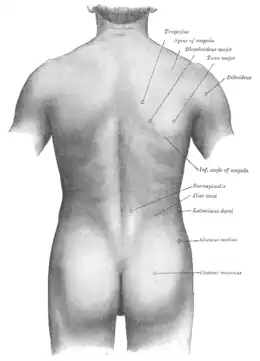

Dos

Dos humain

Le dos humain se compose de sept vertèbres cervicales, douze vertèbres thoraciques (ou dorsales), cinq vertèbres lombaires (ou lombales), cinq vertèbres sacrales et le coccyx.

Toutes les vertèbres (excepté les premières vertèbres cervicales, les sacrales et les coccygiennes) sont séparées les unes des autres par un disque intervertébral. Les centres des vertèbres sont empilés, ce qui fait que leurs arcs forment un tube par lequel la moelle spinale passe. À partir de la moelle spinale, des nerfs passent entre les vertèbres, pour innerver par exemple les jambes et les bras.